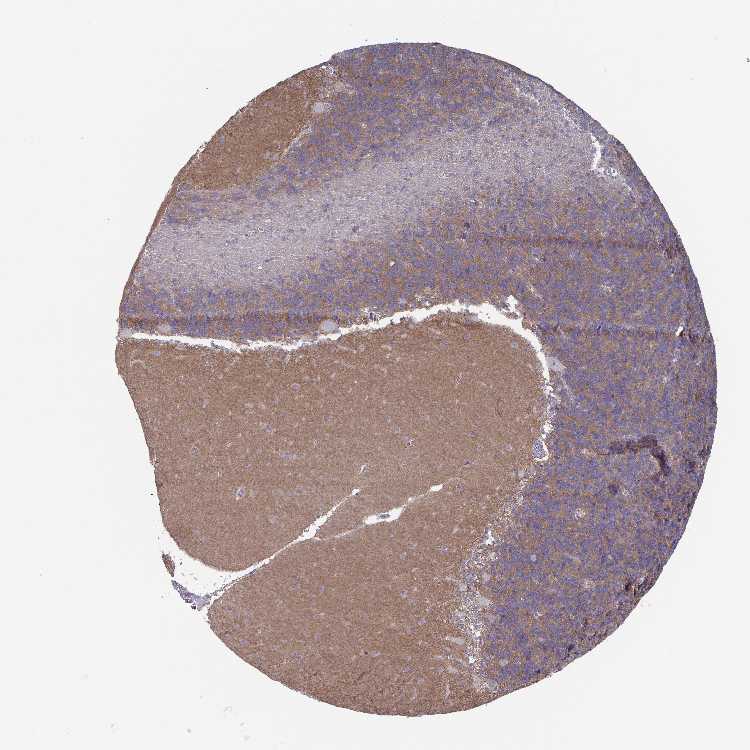

CEREBELLUM - Antibody stainingi

Antibody staining in the annotated cell types in the current human tissue is reported as not detected, low, medium, or high, based on conventional immunohistochemistry profiling in selected tissues. This score is based on the combination of the staining intensity and fraction of stained cells.

Each image is clickable and will lead to virtual microscopy that enables deeper exploration of all samples and also displays staining intensity scores, fraction scores and subcellular localization as well as patient and tissue information for each sample.

Antibody HPA059921

Purkinje cells Not detected

Cells in granular layer Medium

Cells in molecular layer Not detected